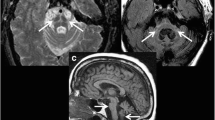

Imaging the Presynaptic Dopaminergic System

Ideally, one would like to be able to image the abnormal Asyn aggregates present in PD neurons. Small-molecule ligands such as BF227 exist which bind to these, but when tagged with an 11C or 18F isotope to make positron emission tomography (PET) tracers, they give low specific signals and they also bind as avidly to extracellular amyloid deposits [24]. As a consequence, imaging in PD aims to detect the consequences of the Asyn pathology. The integrity of the cell bodies in the substantia nigra compacta (SNc) can be imaged structurally with MRI while striatal DA terminal function can be imaged with radiotracer-based PET and SPECT. High field MRI detects a loss of nigrosome 1 signal in the ventrolateral SNc of PD cases [1] while MR sequences sensitive to paramagnetic neuromelanin also show ventrolateral signal loss [2, 25]. Using a bitensor approach, diffusion tensor imaging (DTI) is able to measure the size of the SNc free water pool and has shown that this is significantly increased in PD due to the cell loss [26] (Fig. 1). A 4-year follow-up of the Parkinson’s Progression Markers Initiative (PPMI) PD cohort showed that the posterior nigral free water pool increased along with locomotor disability on the Hoehn and Yahr scale [27].

(a/b) Bitensor DTI of the midbrain. The substantia nigra free water pool is increased in Parkinson’s disease. (Picture from ref [26]: Ofori et al. 2015)